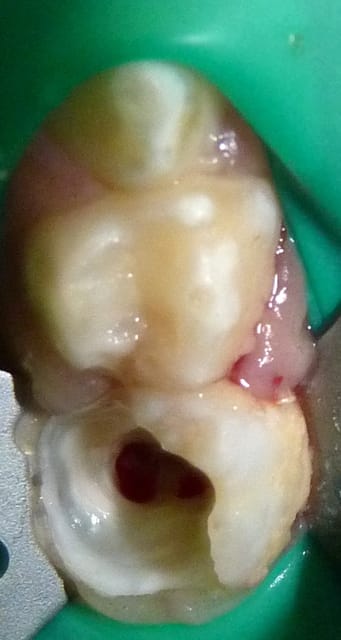

Dans le cas ci-dessous, la 1ère photo est prise après début d’éviction carieuse : sur la 4, on voit déjà la pulpe par transparence. Les tubuli dentinaires d'une dent temporaire sont beaucoup plus larges et nombreux que sur une dent permanente. Ainsi, une carie dentinaire infecte très rapidement la pulpe camérale. Faire une restauration sans pulpotomie dans ce cas aurait probablement abouti à une nécrose à moyen terme.